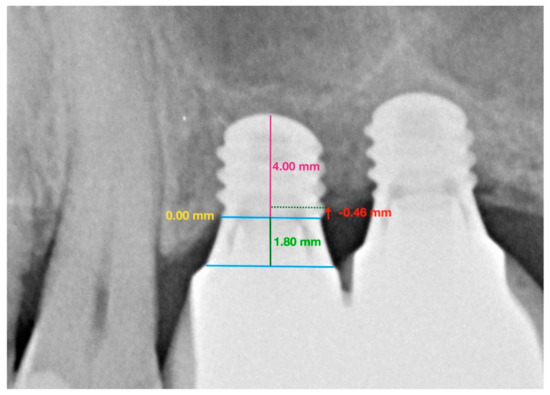

- Two reference points were located (clearly visible in radiographs and easily reproducible) at the join between the implant and the prosthetic crown, i.e., the line representing the prosthetic platform.

- Straumann® Standard Plus (RN/WN) implants have a 1.8 mm polished collar. To scale the implant’s active portion, a perpendicular line was traced to measure the known length of the implant and the height of the polished collar.

- Having calibrated the radiographic image, differentiating between the polished collar and the real implant length, mesial, and distal reference points were established denominated as height 0.